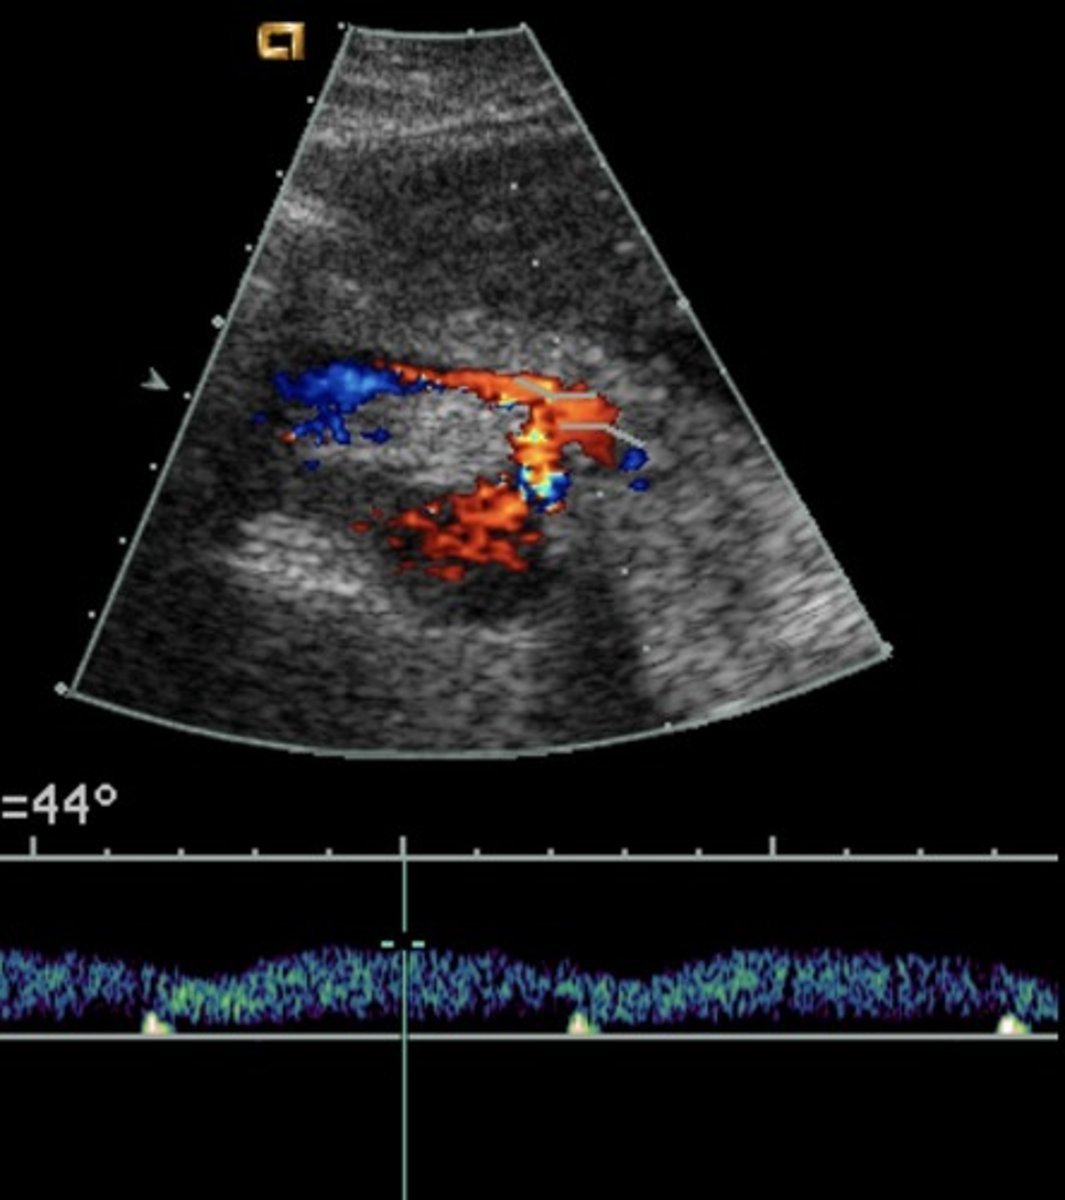

Left Gastric Vein (coronary vein) Doppler Flow

Hepatofugal